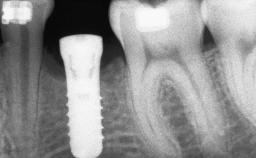

A 46-year-old woman was referred for treatment whose main complaints were mobility of her fixed partial dentures (right maxilla and left mandible) and periodontal bleeding during function. She also reported having taken systemic antibiotics to treat recurrent swelling in the area of the upper left molars. The patient had not seen a dentist for at least 2 years. She did not smoke and had no history of major systemic disease other than two minor orthopedic procedures some years back. The first-visit examination revealed poor plaque control, tooth mobility, periodontal disease, and a residual dentition widely associated with deep periodontal pockets.

# of Implants 3

Type of Implants One-Piece

Bone Volume Deficient vertically or deficient vertically AND horizontally